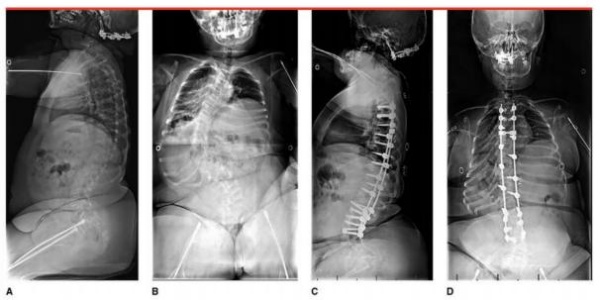

❖ Điều trị vẹo cột sống [5]

- Điều trị khó vì xương loãng và biến dạng thường nặng, tiến triển.

- Điều trị bảo tồn bằng nẹp không hiệu quả giảm vẹo tiến triển vì xương sườn dễ gãy. Một số bệnh nhân có thể cho đeo nẹp cột sống ngực đến xương cùng để cải thiện vận động.

- Điều trị phẫu thuật khi góc Cobb trên 35 độ ở OI thể nặng, Cobb trên 45 độ ở OI thể trung bình.

- Phương pháp: Dùng cấu hình vít nắn chỉnh đi đường sau đa số trường hợp, dùng đường trước với bệnh nhân rất trẻ để tránh hiện tượng trục khuỷu (crankshaft) do nếu hàn phía sau thì phần cột sống phía trước vẫn phát triển ở bệnh nhân trẻ.

- Điều trị phẫu thuật thường khó vì mổ lớn, mất máu nhiều, xương loãng.